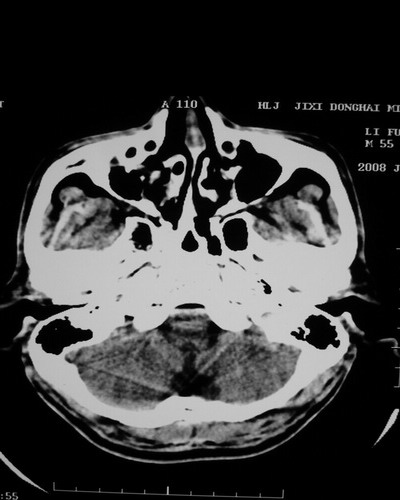

以下是引用随光逐影在2008-1-14 17:26:00的发言:[br]考虑为:甲状旁腺功能低下。需与fahr`s病相鉴别。建议:实验室检查。